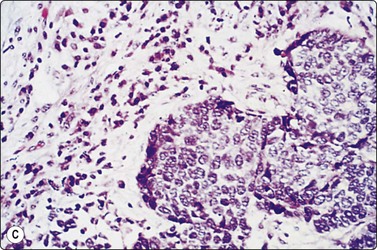

Small cell carcinoma (Figs 8.25-8.29)32,35,36,79,82,83

image

Fig. 8.25 Small cell carcinoma

Loose clusters with some dispersal and smearing artifact (Pap, HP).

Fig. 8.26 Small cell carcinoma

Pleomorphic poorly cohesive cells with little or no cytoplasm; nuclear molding (MGG, HP).

Fig. 8.27 Small cell carcinoma

Small loose cluster showing absence of cytoplasm, finely granular chromatin, inconspicuous nucleoli, nuclear molding and teardrop cells (H&E, HP).

Cell pleomorphism is so distinctive that a diagnosis of malignancy is seldom in doubt (Figs 8.25-8.27). The most immediate impression is the absence or sparseness of cytoplasm rather than the small size of the neoplastic cell (Figs. 8.26 and 8.27). In fact, the cell nuclei may appear larger than similar cells in sputum and this may mislead one into making a diagnosis of non-small cell carcinoma. This difference in size between sputum and aspirated material is due to degenerative changes and shrinkage in sputum. It is sparseness of cytoplasm rather than size which is the most helpful initial clue in differentiating the lesion from other pulmonary carcinomas.

The combination of dispersal with clustering is also important, especially when other small cell neoplasms enter the differential diagnosis (Fig. 8.25). Lymphomas generally do not display such cell cohesion, although large fragments may be dislodged, and in some cases lymphoid cells may form clusters or packets.

Fragility of nuclei is emphasized by tear-drop cells or streaks of smeared nuclear material,226 and the close nuclear apposition and molding so commonly seen in sputum are also evident (Figs 8.26 and 8.27). Uniform coarsely granular ‘salt and pepper’ nuclear chromatin is also a well-recognized feature of this cancer in other sites, but one point of difference from sputum is the frequency of small nucleoli in aspirated material; they are less commonly seen in sputum. This may also be related to the better preservation of cells removed directly from tumor; small nucleoli are also often seen in bronchial brush material. Mitotic figures are usually easily found.